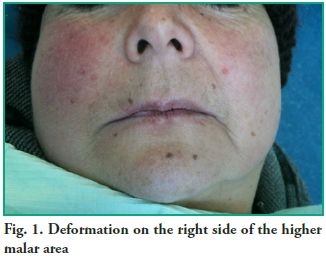

Clinical case A 68-year-old female patient who came to the Emergency Clinic of the School of Dentistry, Udelar, complaining of swelling in the right higher malar area and moderate pain. Intraoral drainage is performed in the vestibular area, near tooth 13, and the patient is prescribed antibiotics (Amoxicillin 875 mg every 8 h). The patient was referred to the Clinic of Oral and Maxillofacial Surgery III with persistence of the swelling but no pain. She has a medical history of controlled but uncompensated hypertension and hypercholesterolemia. She uses upper and lower full prostheses. A deformation in the right side of the face with obliteration of the nasolabial fold (Fig. 1) was observed in the clinical examination of the face. The intraoral examination showed that

Clinical case A 68-year-old female patient who came to the Emergency Clinic of the School of Dentistry, Udelar, complaining of swelling in the right higher malar area and moderate pain. Intraoral drainage is performed in the vestibular area, near tooth 13, and the patient is prescribed antibiotics (Amoxicillin 875 mg every 8 h). The patient was referred to the Clinic of Oral and Maxillofacial Surgery III with persistence of the swelling but no pain. She has a medical history of controlled but uncompensated hypertension and hypercholesterolemia. She uses upper and lower full prostheses. A deformation in the right side of the face with obliteration of the nasolabial fold (Fig. 1) was observed in the clinical examination of the face. The intraoral examination showed that